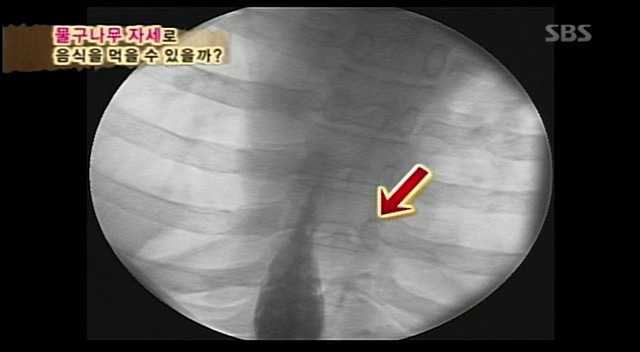

오~ 동엽신이 초코파이가 올라간다고하는데

초코파이를 먹은건가봄

이번에는 응아같은게 위로 올라감

확실히 서서먹는것보다 속도가 훨씬 느리게

음식이 위를향해감